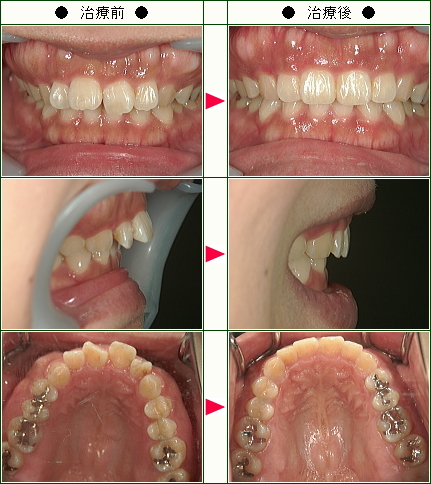

☆歯のデコボコ矯正症例(まほ様 21歳 女性)